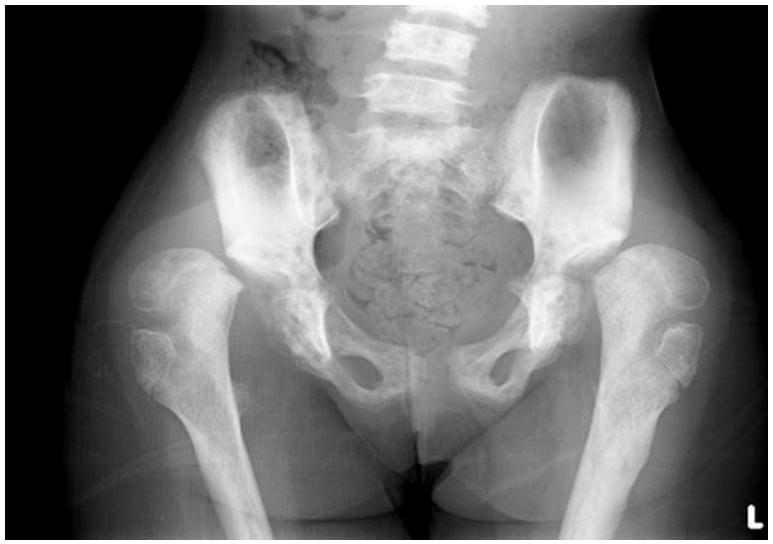

Figure 4.

Radiograph of pelvis shows bilateral hip dislocations with valgus slip of capital femoral epiphysis and irregular cortex with increased bone density of iliac bones.

Radiographic evaluation revealed thoracolumbar scoliosis with anterior central concavity of vertebral bodies (Figs. 3a and 3b). She had bilateral dislocation of hips with valgus slip of the capital femoral epiphysis, irregular cortices of the femur and varied bone density (Fig. 4). Spine and iliac bones were sclerotic. Her long bones were slender. Radiography of both hands showed short 4th and 5th metacarpals and hypoplastic distal phalanges (Fig. 5a). There were short 3rd and 4th metatarsals (Fig. 5b). Radiographs of knees were unremarkable (Figs. 5c and 5d)